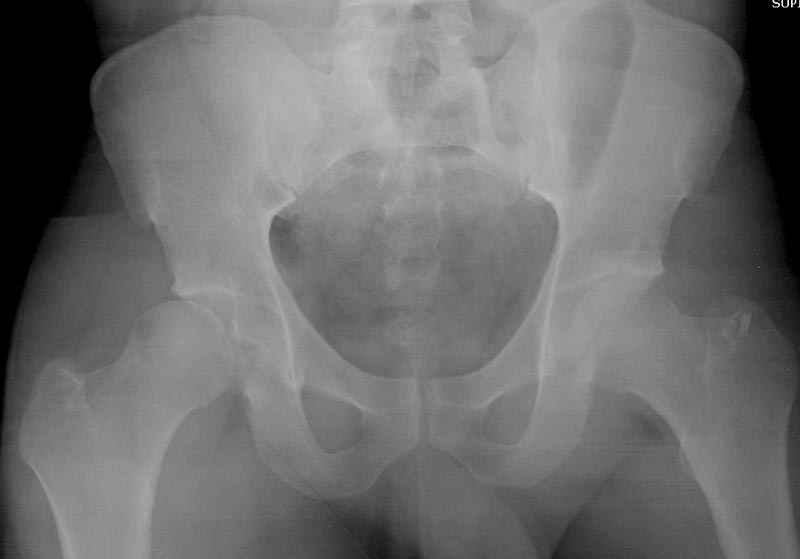

5:24 Рентгенограмма таза, вызывают врача ортопеда (снимок N1), его диагноз: закрытый переломо-вывих правого тазабедренного сустава, получает добро на закрытую репозицию в приемном отделении

5:38 Дважды неудачная попытка закрытой репозиции в приемном отделении

6:20 ответстенный врач принимает решение о репозиции в условиях операционной, предупреждаются родственники и больной, что при неудачной закрытой репозиции, о возможности открытой репозиции и фиксации задней стенки вертлужной впадины.

На рисунке N1 предоперационный план лечения ложного сустава шейки бедра- линия ложного сустава, угол и направление введения импланта, клиновидная остеотомия в градусах и миллиметрах, второй снимок после коррекции, расчет, на сколько удлиняется конечность и размеры импланта;

Интересно бы посмотреть рентгенограмму таза (оба сустава) а также рентгенгорамму с захватом коленных суставов (по Dror Paley).